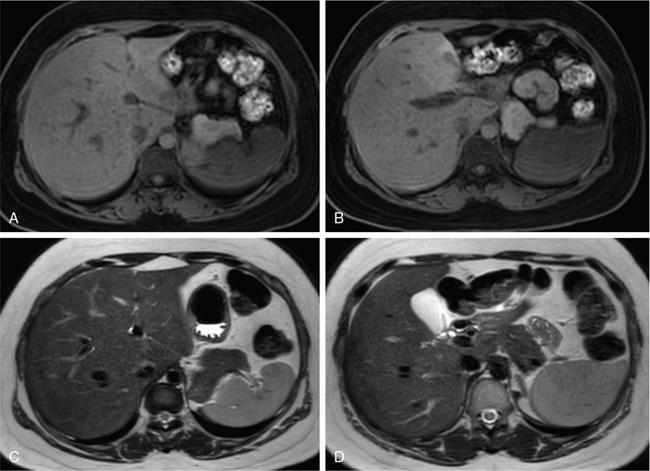

Ritu K. Kashikar, Shrinivas B. Desai Imaging is the mainstay of noninvasive diagnosis of the spectrum of abdominal pathologies or proving absence off thereof. Knowledge of normal anatomy and important normal variants is thus essential for the radiologist in order to avoid misinterpretation or erroneous diagnosis. This chapter highlights the normal anatomy of the hepatobiliary systems including the blood vessel and draining ducts and discusses relevant anatomical variants which may have important clinic implications. The liver is the largest abdominal organ, occupying the right upper abdominal quadrant and is in close approximation with the diaphragm, stomach and the gallbladder. It is largely covered by the costal cartilages. The liver is encapsulated by Glisson’s capsule which is a dense layer of connective tissue. It is covered by peritoneum, except in the regions of gallbladder fossa, fossa for inferior vena cava (IVC), and the bare area. The bare area is the posterocranial aspect of the liver, adjacent to the dorsal body wall, which is not covered by peritoneum. The liver has two surfaces, the convex diaphragmatic surface and a concave visceral surface. The slit in the hepatic hilum is called the porta hepatis and is penetrated by the right and left hepatic ducts (LHDs), hepatic artery and portal vein (PV). The distal portion of the lesser omentum is called the hepatoduodenal ligament and contains the common bile duct (CBD), hepatic artery, PV, nerves of liver and lymphatics. The liver has dual blood supply with hepatic artery providing 25% of hepatic blood and rest by portal vein (Fig. 9.2.1). Five ligaments connect the liver to the undersurface of the diaphragm. These include the falciform, the coronary and two lateral ligaments, all of which are peritoneal folds. The fifth ligament is a fibrous cord-like structure and represents the obliterated umbilical vein. The peritoneum invaginates into the liver parenchyma leading to formation of fissures. There are four normal fissures: fissures for the ligamentum teres, ligamentum venosum and gallbladder and the transverse fissure (Fig. 9.2.2). The liver is organized into microscopic functional units called lobules or acini. A central terminal hepatic venule surrounded by four to six terminal portal triads form a polygonal unit called the hepatic lobule. The terminal portal triad branches line the periphery of the unit. Between the terminal portal triads and the central hepatic venule the hepatocytes are arranged in one cell thick plates, surrounded by sinusoids. The blood flows from the terminal portal triad through sinusoids into terminal hepatic venule. Bile formed within the hepatocytes empties into terminal canaliculi which coalesce into the bile ducts (Fig. 9.2.3). This structure of the functional hepatic unit forms the basis of various functions of the liver. The normal relations of the liver are: The liver can be divided into right, left and caudate lobes. The right and left lobes are separated by the interlobular fissure and is oriented along a line passing through the gallbladder fossa inferiorly and the middle hepatic vein (MHV) superiorly (Fig. 9.2.4). This plane runs from the left of the IVC to the left of the gallbladder fossa and is a called the Cantlie’s line. Use of standardized, segmental anatomy is imperative because it facilitates communication and treatment planning. The segmental anatomy of liver is primarily based on vascular anatomy. The right lobe is divided into anterior and posterior sectors by of the right hepatic vein (RHV). The left lobe is divided into medial and lateraI sectors by an oblique plane connecting the left hepatic vein (LHV) and the falciform ligament. The liver is divided into upper and lower segments at the level of main portal vein (MPV) bifurcation (Fig. 9.2.5). Various systems are used in classification of liver anatomy. These are discussed in Table 9.2.1. The Couinaud’s system is the most commonly used and divides eight sections/segments which are discussed in details below (Table 9.2.2). 1. Segment 1 – Caudate lobe Bounded anteriorly and medially by the fissure for ligamentum venosum (Fig. 9.2.6). 2. Segment 2: Superior segment of the left lateral sector/section Bounded medially by falciform ligament and inferiorly by plane of MPV, also known as the posterior lateral sector (Bismuth, FCAT) (Fig. 9.2.7). 3. Segment 3: Inferior segment of left lateral sector/section Bounded medially by the falciform ligament and superiorly by the plane of the MPV bifurcation, also referred to as lateral anterior sector (Bismuth, FCAT) (Fig. 9.2.8). 4. Segment 4: Left medial sector/section Bounded laterally by falciform ligament and medially by Cantlie’s line (Fig. 9.2.9). 5. Segment 5: Inferior segment of the right anterior sector/section Bounded anteriorly by the gallbladder fossa and posteriorly by the plane of the RHV, superiorly bounded by the plane of MPV bifurcation (Fig. 9.2.10). 6. Segment 6: Inferior segment of the right posterior sector/section Bounded anteriorly by plane of the RHP and superiorly by the plane of the MPV bifurcation (Fig. 9.2.11). 7. Segment 7: Superior segment of the right posterior sector/section Bounded anteriorly by the plane of the RHV and inferiorly by the plane of the MPV bifurcation (Fig. 9.2.12). 8. Segment 8: Superior segment of the right anterior sector/section Bounded anteriorly by the plane of the gallbladder fossa and MHV, posteriorly bounded by the plane of the RHV and inferiorly by the plane of the MPV bifurcation (Fig. 9.2.13). Owing to its broad area of contact with the anterior abdominal wall, the liver is an ideal organ for evaluation with sonography. Ultrasound is commonly used for evaluation of size of the liver. On longitudinal scans obtained through the midhepatic line, if the liver measures 13 cm or less, it is normal in 93% of individuals (Fig. 9.2.14). The size of liver in various planes is discussed in chapter on normograms. When the area of contact between the liver and the anterior border of the right kidney, exceeds below two thirds of the kidney, the liver is considered as enlarged. The normal liver is homogeneous with fine echoes and appears evenly bright. The hepatic veins, PV and fissures interrupt the homogeneity of the liver parenchyma (Fig. 9.2.15). The parenchymal echogenicity may vary depending on the equipment, transducer and gain settings and should be judged by comparison with internal references like right renal cortex, body of the pancreas and PV walls. When compared with the adjacent normal right renal cortex the liver normally appears hyperechoic or isoechoic. The pancreas in a young individual is hypoechoic compared to the liver, and isoechoic in middle aged adults. As age progresses and fatty infiltration of the pancreas occurs, the pancreas appears hyperechoic to the liver. The liver is hypoechoic to the spleen. The normal liver reveals a density of 55–65 HU on nonenhanced scan and should appear homogenous with the exception of hypodensity in the regions of vessels and fissures. The liver parenchymal enhancement is minimal the arterial phase, with increase in density by only approximately 10 HU. This phase is usually to access vascular anatomy and to detect neovascular enhancing lesion like HCC, metastasis. Considering the fact that 75% of heptic venous supply is from the PV, the normal hepatic parenchyma shows maximum enhancement in the portal venous phase. During the venous/delayed phase the hepatic attenuation starts falling (Fig. 9.2.16). The hepatic fissures appear as linear fat containing structures. All the four fissures are well identifies on CT (Figs. 9.2.17–9.2.20). Normal liver should demonstrate uniform T1 signal similar or isointense to the paraspinal muscles and slightly hyper intense to the spleen. No signal drop should be seen on in or opposite phase. On T2W1 images liver appears slightly hyperintense to paraspinal muscles, isointense to pancreas and hypointense to spleen (Fig. 9.2.21). Following administration of extracellular contrast agents the normal liver parenchyma enhances on PV phase similar to that seen on CT. The arterial phase is preserved to determining vascular anatomy, variants and tumoural enhancement. Gadoxetic acid (Eovist) and gadobenate dimeglumine (MultiHance) are hepatobiliary agents showing excretion by the liver. In the case of gadoxetic acid, hepatic excretion is ~50%, which allows imaging in the hepatobiliary phase at ~20 minutes following injection. Gadobenate has only 3%–5% biliary excretion with hepatobiliary phase at approximately 40 minutes (Fig. 9.2.22). This property makes these agents useful in detection of nonhepatocyte containing lesions which appear hypointense to background liver on hepatobiliary phase. Hepatic anatomic variants are relatively common and represent normal interindividual variation of liver morphology. Normal Anatomic Variants Anatomic anomalies Accessory and pseudofissures may be seen in the liver. True accessory fissures result from infolding of the peritoneum usually along the undersurface of the liver and are rare. The inferior accessory fissure is the commonest accessory fissure and divides the posterior segment of the right hepatic lobe into lateral and medial portions. Diaphragmatic slips may cause indentation over the liver surface and are not commonly seen on imaging (Fig. 9.2.23). Leftward extension of the lateral segment of the left hepatic lobe appearing as a crescentic density that wraps around the spleen is referred to as sliver of liver. The left lobe of the liver may exhibit various forms: leaf like; spatular; truncated pyramid/wedge shaped; and a bifid appearance (Fig. 9.2.24). Elongated left lobe may be mimic splenomegaly, perisplenic hypoechoic collections or less commonly tumours. Imaging clues to diagnosis are establishing contiguity with liver and visualization of parenchymal vessels coursing through. The portion of the liver that extends medially from the right lobe between the IVC and fissure for ligamentum venosum is called the caudate lobe. The caudate lobe is divided inferiorly into a lateral caudate process and a medial papillary process. The medial papillary process projects medially towards the pancreatic head and has applied importance (Fig. 9.2.25). Riedel’s lobe is a tongue-like projection from the anterior aspect of the right lobe and the most common accessory lobe of the liver. It is seen most frequently in asthenic women. The reported prevalence of RL, ranges from 3.3% to 14.5% and the prevalence is higher in women than in men. It can be 20 cm or more in length and may extend up to the iliac fossa. It is usually asymptomatic and is discovered incidentally (Fig. 9.2.26). Accessory liver lobes are defined as a supernumerary lobe of normal hepatic parenchyma in continuity with the liver. This is a rare entity and usually occurs as a result of congenital ectopic hepatic tissue, although rarely may occur as a result of trauma or surgery. Various systems are proposed for classification of ALL. Another method of classification has been proposed based on biliary drainage and presence or absence of capsule. Accessory lobes can be readily diagnosed and characterized on CT or magnetic resonance imaging (MRI) done for related or unrelated conditions. CT shows the lesion as a soft–tissue density mass attached to the liver and isodense to the organ. The portal/hepatic venous branches can be seen coursing through it, in contiguity with the liver (Fig. 9.2.27). The coeliac axis trifurcates into common hepatic, splenic and left gastric arteries at the level of T12–L1. The common hepatic artery becomes the proper hepatic artery after origin of the gastro-duodenal artery. The hepatic artery proper ascends anterior to the PV and medial to the CBD and divides in to right and left hepatic artery (LHA). Occasionally the middle hepatic (segment 4) artery arises from hepatic artery proper. The hepatic artery appears as a tubular hypoechoic structure and shows antegrade flow on Doppler (Fig. 9.2.28). Normally the resistive index is low ranging between 0.55 and 0.7. The hepatic artery, its anatomy, branches, course, calibre are best evaluated on arterial phase of dynamic CT (Fig. 9.2.29). This is also the preferred modality prior to hepatobiliary surgical planning. Contrast-enhanced MRI also shows the above details but spatial resolution is lower. Road map of the arterial vascularity of the donor and recipient is a prerequisite for transplant surgery and complex hepatobiliary surgery. Detailed hepatic arterial anatomy and its variations have its significance in liver surgeries and interventional hepatic procedures, relative to the hepatic lobe involved. A classification method was described by Michel et al. in 1955, and is discussed in Table 9.2.3 (Fig. 9.2.30). I: standard anatomy ~60% (range 55%–61%) II: replaced LHA ∼7.5% (range 3%–10%) III: replaced RHA ~10% (range 8%–11 %) IV: replaced RHA and LHA ~1% V: accessory LHA from LGA ~10% (range 8%–11%) VI: accessory RHA from SMA ~5% (range 1.5%–7%) VII: accessory RHA and LHA ~1% VIII: accessory RHA and LHA and replaced LHA or RHA ~2.5% IX: CHA replaced to SMA ~3% (range 2%–4.5%) X: CHA replaced to LGA ~0.5% Other unclassified variants are: The two most common variants are the replaced right hepatic artery (RHA) arising from the SMA (Fig. 9.2.31) and replaced LHA arising from the left gastric artery (Figs. 9.2.32–9.2.34). Segment 4 artery – Middle hepatic artery (MHA) The middle hepatic artery usually arises from the LHA, it may, however, arise from the RHA (Fig. 9.2.35). The knowledge regarding origin of MHA is imperative in transplant surgery. The MHA can arise from RHA in Patients with replaced LHA. In patients with replaced RHA, the MHA arises from LHA (Fig. 9.2.36). Because of the considerable variability of hepatic arterial anatomy, assessment of this anatomy is crucial in the preoperative evaluation of potential living liver donors. Relevance of donor and recipient arterial anatomy is discussed in details in chapter on liver transplant. The relationship between the arterial variant and tumour is important to establish prior to major surgeries. Injuries to aberrant hepatic vessels and secondary ischaemic biliary strictures can be avoided. A replaced RHA has a more posterior course and long length. This variant may be advantageous in patients undergoing right lobar resection. However, there is greater propensity of involvement of replaced RHA by pancreatic head. The radiologist must be vigilant in reporting this variant (Fig. 9.2.37). Accessory RHA can, however, be sacrificed even if encased by neoplasm. An accessory LHA needs to be ligated separately in surgeries where blood supply in the porta hepatis is occluded. Replaced LHA from LGA maybe injured in case of surgeries at the level of hiatus. Hence this variant should be informed to surgeon in patients undergoing gastric surgeries. Preoperative mapping of the hepatic arterial anatomy prior to placement of intraarterial chemotherapy pumps is essential because it helps in deciding whether the candidate is suitable for the procedure and also if technical modifications are needed. The intraarterial infusion pump should be placed in the dominant hepatic artery as proximal as possible, but beyond GDA origin. Inpatients with standard anatomy, the pump is usually placed in the hepatic artery prior just after GDA origin. The location of pump can be modified in patients with variant anatomy, based on origin of GDA and dominant hepatic vessel. The PV is the main vessel in the portal venous system and drains blood from the gastrointestinal tract and spleen to the liver.